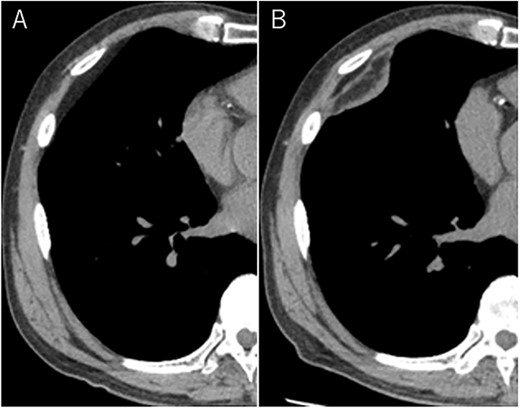

A 72-year-old man with a history of hypertension and left renal cancer (Stage I) was referred to us with a mass in the right chest wall on post-operative follow-up chest computed tomography (CT) for renal cancer. He had a smoking history of 20 pack-years and had no exposure to environmental fumes or dust. Physical examination results were unremarkable. The laboratory findings were within normal limits. Pulmonary function tests and cardiovascular examinations revealed normal results. Chest CT revealed mixed density mass (8.0 × 5.0 × 3.0 cm) located in front of thoracic wall in the third to sixth right intercostal space. The tumor can be revealed as thoracic wall fat (7.8 × 4.8 × 1.2 cm) on CT 1 year before (not considered as abnormal), and it was progressively increased in size and the density changed (Fig. 1A and B). Magnetic resonance imaging (MRI) showed a fatty mass of heterogenic density. T2 high foci (Fig. 2A) and irregular marginal enhancement of the tumor were observed (Fig. 2B). Maximal standard uptake value (SUVmax) of 18F-fluorodeoxyglucose positron emission tomography (FDG-PET) was 3.78 (Fig. 3). Based on these radiological image findings, we scheduled surgery with suspicion of liposarcoma. During the surgery, the patient was placed in the lateral decubitus position. We made 1.5-cm incision in the sixth intercostal space along the posterior axial line for thoracoscopy. We found dense adhesions between the chest wall tumor, lung (front part of all three lobes of the right lung) and diaphragm. We made a 30-cm incision in the fourth intercostal space and resected the tumor along with lung (wedge resection of the front part of all three lobes of the right lung), diaphragm and third to sixth ribs and intercostal muscle. The chest wall defect was 25 × 15 cm and the diaphragm defect was 8 × 5 cm. For reconstruction, the mesh was placed and sutured to the diaphragm and the chest wall. Pathological examination revealed the well-circumscribed tumor with fibrous adhesion between the ribs, lung and diaphragm (Fig. 4A). Microscopically, the tumor consisted of mature fat tissue. There were fat necrosis inflammatory changes in the marginal area of the tumor with foamy macrophages and multinucleated giant cells (Fig. 4B and C). Fluorescence in situ hybridization examination for murine double-minute 2 was negative. Based on these findings, a chest wall lipoma was diagnosed. The post-operative course was uneventful. The patient was followed up for 24 months without evidence of recurrence.

(A) Tumor (T) with fibrous adhesion between ribs (R), lung (L) and diaphragm (D); (B) matured fat tissue consist the tumor; (C) marginal area of the tumor fat necrosis and inflammatory changes with foamy macrophage and multinucleated giant cells.

Pathological findings in this case showed fat necrosis and inflammatory changes in the marginal area of the tumor, with foamy macrophages, and multinucleated giant cells. These changes may cause the malignant featured images, such as heterogenic density, enhancement on MRI and high SUVmax of FDG-PET. In addition, these changes may cause dense adhesion. Several lipomas with fat necrosis has been reported [8], but none of them have intrathoracic origin. In addition, no other cases with conspicuous radiological image change have been reported as in our case.